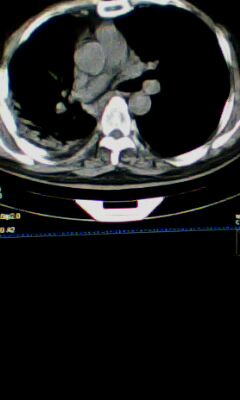

标题: CT25675:男 71 肺癌部分切除术后 3年 [打印本页]

标题: CT25675:男 71 肺癌部分切除术后 3年

两肺感染性病变,右侧肺膨胀不全,左侧上叶结节影及左侧颈部淋巴结肿大建议复查。

1)两肺感染性病变。2)右侧胸膜增厚。3)冠状动脉及主动脉钙化。

右肺癌切除术后。

右肺炎症,左肺炎症。

右侧胸膜肥厚。

1.右肺符合肿瘤切除术后ct表现。

2.左肺炎症。

术后改变,双肺内纤维索条影考虑与放疗有关。